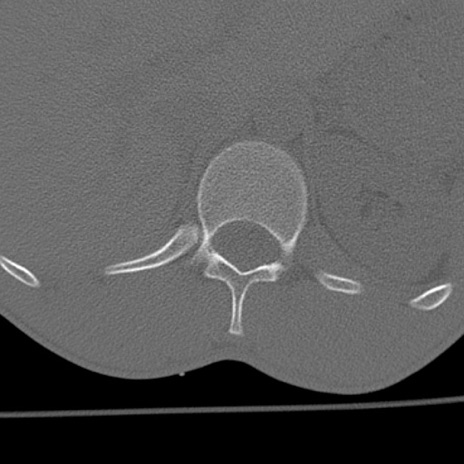

症例3 腰椎CT(横断像)

腰椎CT